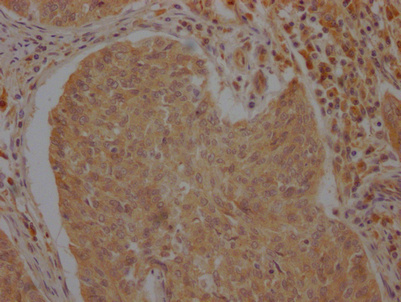

IHC image of CSB-PA002277LA01HU diluted at 1:100 and staining in paraffin-embedded human cervical cancer performed on a Leica BondTM system. After dewaxing and hydration, antigen retrieval was mediated by high pressure in a citrate buffer (pH 6.0). Section was blocked with 10% normal goat serum 30min at RT. Then primary antibody (1% BSA) was incubated at 4°C overnight. The primary is detected by a Goat anti-rabbit polymer IgG labeled by HRP and visualized using 0.05% DAB.